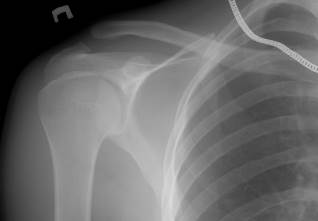

Разрыв Ключично-Акромиального Сочлинения

Разрыв акромиально-ключичного сочленения происходит очень часто у людей, которые ведут активный образ жизни. И конечно же в группу риска входят и люди, которые занимаются профессионально спортом. Чтобы окончательно понять, о чем идет речь, нужно немножко отвлечься и вспомнить анатомию. Соединенные между собой ключица, лопатка и кость плеча образовывают между собой плечевой пояс. Место соединения лопатки и ключицы является мало подвижной частью тела. Это сочленение покрыто сухожильями, чем фиксируют его положение. Кроме этого на концах сустава размещена специальная камера, которая наполнена жид. Разрыв связок АКС Травмы плечевого сустава в общем и акромиально-ключичного сочленения. Разрыв связок АКС. Травмы плечевого сустава в общем и акромиально-ключичного сочленения. Мобильный кондиционер ballu bpac-12 ce отзывы.

Анатомия акромиально-ключичного сустава. Акромиально-ключичный сустав состоит из двух костей, которые соединены прочно друг с другом при помощи суставной капсулы и связок. При этом между костями сохраняется некоторая подвижность, что необходимо для увеличения амплитуды движений в плече. Суставные концы костей покрыты суставным хрящом. Суставной хрящ имеет очень гладкую скользкую поверхность, благодаря чему сила трения при движении суставных концов ключицы и акромиона минимальна. Благодаря упруго-эластической консистенции суставной хрящ ключично-акромиального сустава выполняет также функцию амортизатора, смягчая ударные нагрузки на кости плечевого пояса.

В отличие от других суставов нашего тела, например, тазобедренного, плечевого или коленного объем движений в ключично-акромиальном суставе значительно ограничен - данное сочленение относится к низкоподвижным суставам, так как движения суставных концов костей в нем происходят только при активных движениях руки и в довольно незначительной степени. Акромиально-ключичный сустав (Articulatio acromioclavicularis) образован сочленением акромиально-суставной поверхности акромиального конца ключицы и суставной поверхности акромиона, расположенной на внутреннем крае акромиона лопатки. Обе суставные поверхности слегка изогнуты, и в 1/3 случаев между ними располагается суставной диск, в котором иногда может быть отверстие. Плоскость наклона обеих суставных поверхностей такова, что суставная полость образует с горизонтальной плоскостью тупой угол, открытый медиально и вверх. В связи с этим косо срезанная суставная поверхность ключицы опирается на суставную поверхность акромиона лопатки. Этим объясняется факт смещения ключицы кверху при вывихах в акромиально-ключичном суставе. Сверху суставную капсулу подкрепляет акромиально-ключичная связка.

Все сочленение укрепляется мощной клювовидно-ключичной связкой, расположенной в стороне от сустава. Эта связка состоит из двух пучков волокон, начинающихся от основания клювовидного отростка лопатки и прикрепляющихся к конусовидному бугорку и трапециевидной линии нижней поверхности акромиального конца ключицы. Топографическая карта россии. Пучок расположенный латерально и кпереди, получил название трапециевидной связки, а лежащий медиально и кзади – конусовидной связки. В акромиально-ключичном суставе возможны движения вокруг трех осей, но амплитуда их незначительная, так как связки ограничивают подвижность сустава. Повреждения акромиально-ключичного сустава возникают обычно при падении на область плечевого сустава, редко с высоты собственного роста, чаще – при падении с велосипеда, мотоцикла и т.п.

Лопатка вместе со всей верхней конечностью как бы «отрывается» от ключицы, которая, упираясь в I ребро, утрачивает связь с акромионом. В тех случаях, когда повреждение ограничивается разрывом ключично-акромиальных связок, наблюдается неполный вывих или подвывих акромиального конца ключицы. Если же разрываются мощные ключично-клювовидные связки (трапециевидная и конусовидная), происходит полный надакромиальный вывих ключицы. Ретракция трапециевидной мышцы смещает ключицу кверху и кзади, лопатки и вся верхняя конечность в вертикальном положении больного в силу тяжести смещаются книзу. По данным разных авторов, вывихи акромиального конца ключицы составляют от 1 до 17,2% среди других вывихов и занимают третье место, уступая вывихам плеча и предплечья. Классификация повреждений акромиально-ключичного сочленения (А.А.

Лапусто, П.И. (1) По степени тяжести выделяют повреждения: I степени - надрыв ключично-акромиальной связки характеризуется болью в проекции ключично-акромиального сочленения. На R-граммах видимых повреждений не отмечено, иногда имеется незначительное (2—3 мм) расширение суставной щели по сравнению со здоровой конечностью. Ключично-клювовидная связка цела; II степени - разрыв ключично-акромиальной связки, надрыв волокон ключично-клювовидной связки. Травма характеризуется болью в проекции ключично-клювовидного сочленения, выстоянием акромиального конца ключицы, положительным симптомом «клавиши». На R-граммах имеется расширение суставной щели более 5 мм. Верхний край ключицы выступает над акромионом до половины своего диаметра; III степени - разрыв ключично-акромиальной и ключично-клювовидной связок характеризуется болью, нарушением функции верхней конечности.

Симптом «клавиши» резко положительный, отведение верхней конечности ограничено. На R-граммах имеется выраженное расширение суставной щели (более 7 мм). Ключица смещена кверху более чем на диаметр акромиона; IV степени - редко встречающиеся случаи - задний вывих, вылущивание акромиального конца ключицы по типу «кожуры банана» и др. (2) По времени, прошедшему с момента получения травмы, повреждения делятся на: свежие - с момента травмы прошло не более 3 суток; несвежие - от 3 суток до 3 недель; застарелые - более 3 недель.